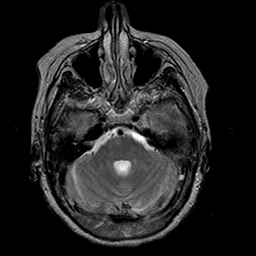

Stroke:T2-weighted MR #1 -- Slice #6

[Home][Help][Clinical] Slice 6